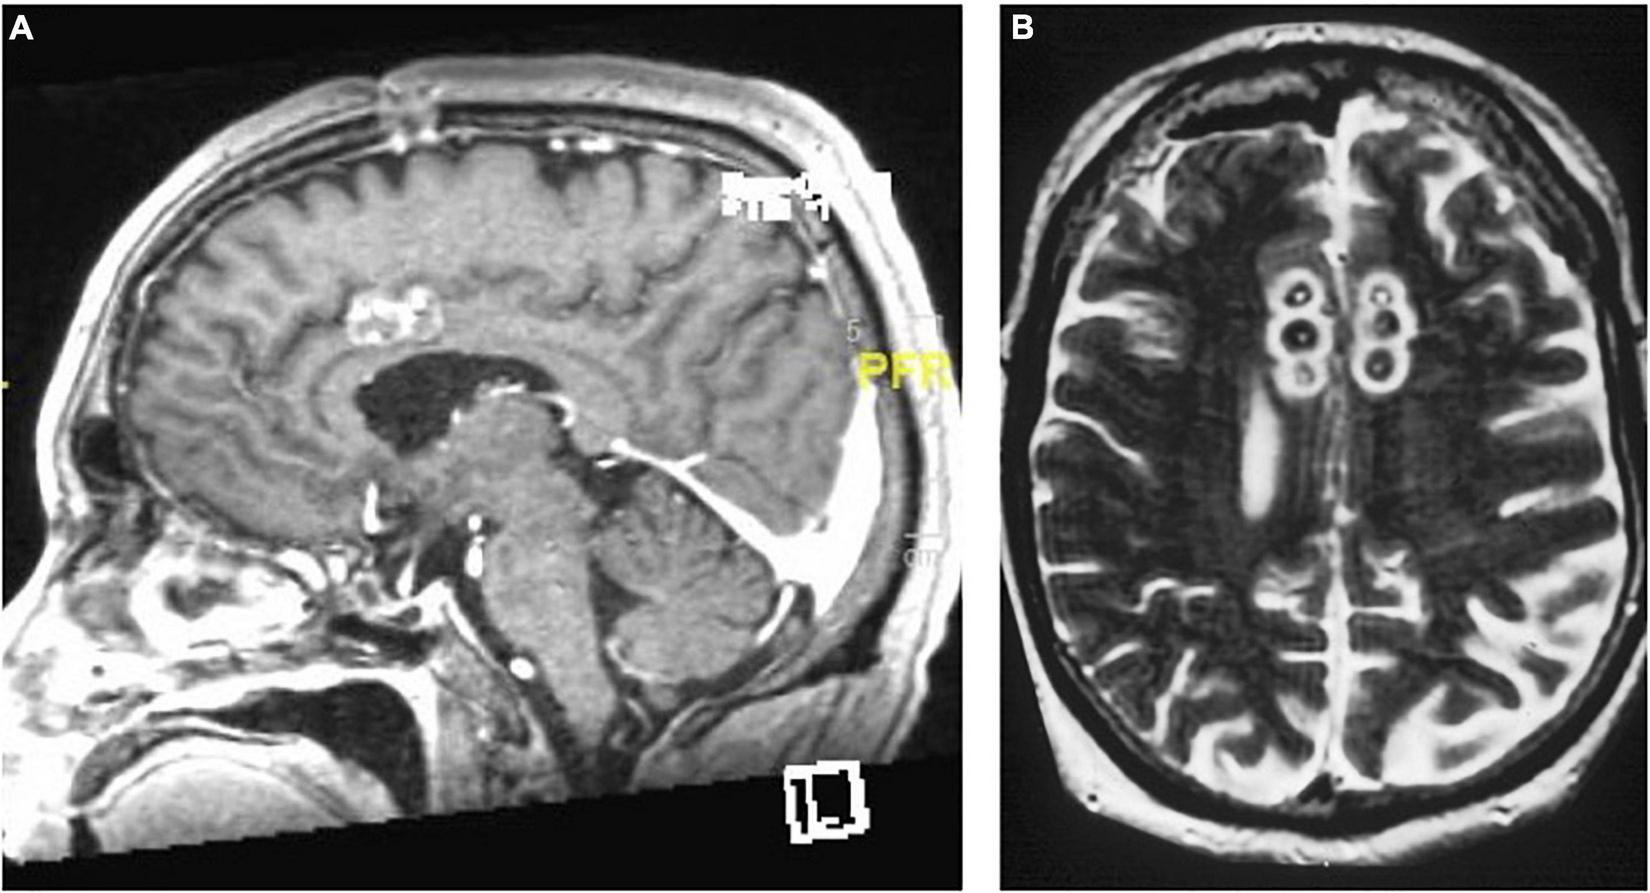

FIGURE 7

Limbic leucotomy. (A) Sagittal T1-weighted and (B) Axial FLAIR MRI of limbic leucotomy lesions.

The modern limbic leucotomy is performed through bilateral burr holes, beginning with a single anterior cingulotomy lesion using a 10 mm exposed electrode at the aforementioned coordinates. Targeting for the subcaudate tractotomy lesion in the posteroinferomedial quadrant of the frontal orbital cortex begins just above the floor of the anterior cranial fossa, 7 mm lateral to midline and 12–15 mm anterior to the anterior commissure. The same 10 mm exposed electrode is inserted and heated to 85°C for 60 s and then withdrawn 5 mm and heated again to create a lesion 15 mm in height and 10 mm in diameter. The medial lesion extends into subcallosal cingulate gyrus (CG 25). A second lesion is placed 14 mm from the midline on the same plane using similar parameters. The upper portion of this lesion should extend into the inferior portion of the anterior limb of the internal capsule (Montoya et al., 2002; Figure 7).